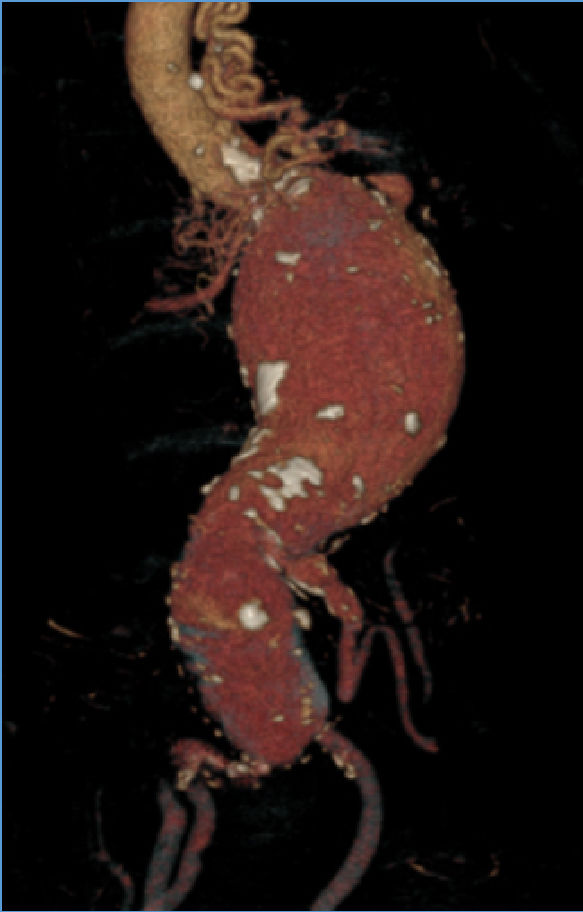

病例:复杂TAAD多次手术后,IIIc型内漏

术后2年随访:动脉瘤增大、左肾支架脱出

★ 大动脉瘤或偏心性动脉瘤术后

如果突然体位变化,有可能主体支架移位导致分支支架从窗口或内脏血管附着处脱出,引起内脏动脉急性阻塞和缺血。